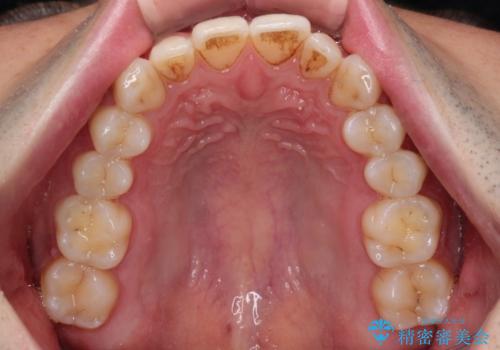

初診時の歯並びの状態としては、下顎に中等度のがたつき(叢生)がある状態でした。

抜歯は行わず下顎の奥のスペースを利用して歯をスライドする方法の他に親知らずの抜歯そして上下ともに歯列弓の拡大やディスキング(歯と歯の間の隙間を作る処置)を行い叢生を改善しました。

歯の大きさの不揃いが原因の正中のズレは、ディスキング量を調整することで合わせました。

矯正装置としてはマウスピースを使用しています。